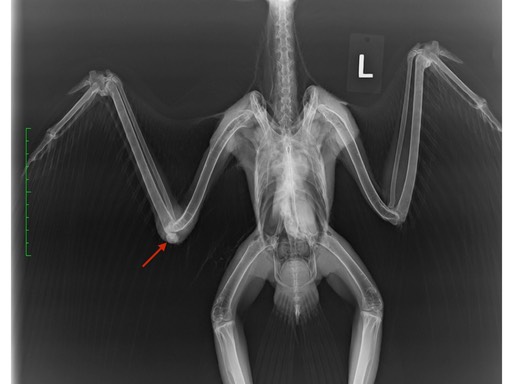

Two of the Red-tailed Hawks had both humerus and femur fractures. One was shot, the other was hit by a car. In the first radiograph the arrows point to damage caused by one projectile. If you look closely, you will see a tiny metal fragment at the tip of arrow one. Many metal fragments and a humerus fracture are visible at arrow 2. Although there are no metal fragments visible at arrow 3, necropsy results indicated the projectile was responsible for the femur fracture. The arrows in the second radiograph point to the humerus and femur fractures caused by the bird being struck by a vehicle.